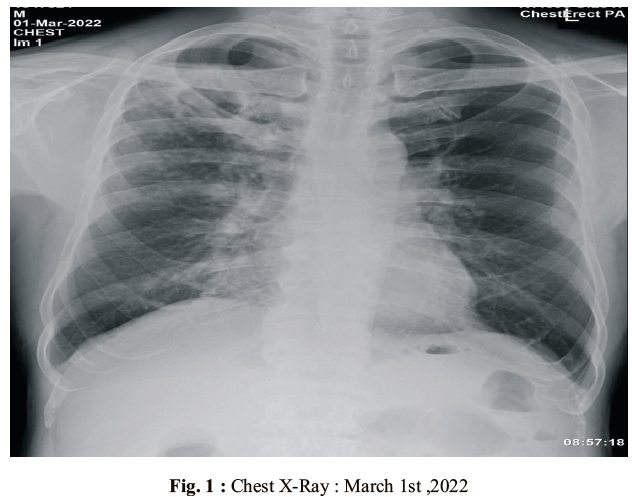

Unusual cause of Intractable Hiccups – A case report

Arathy Radhakrishnan, Siby Joseph, Amit Jose (Author)

2726-2728